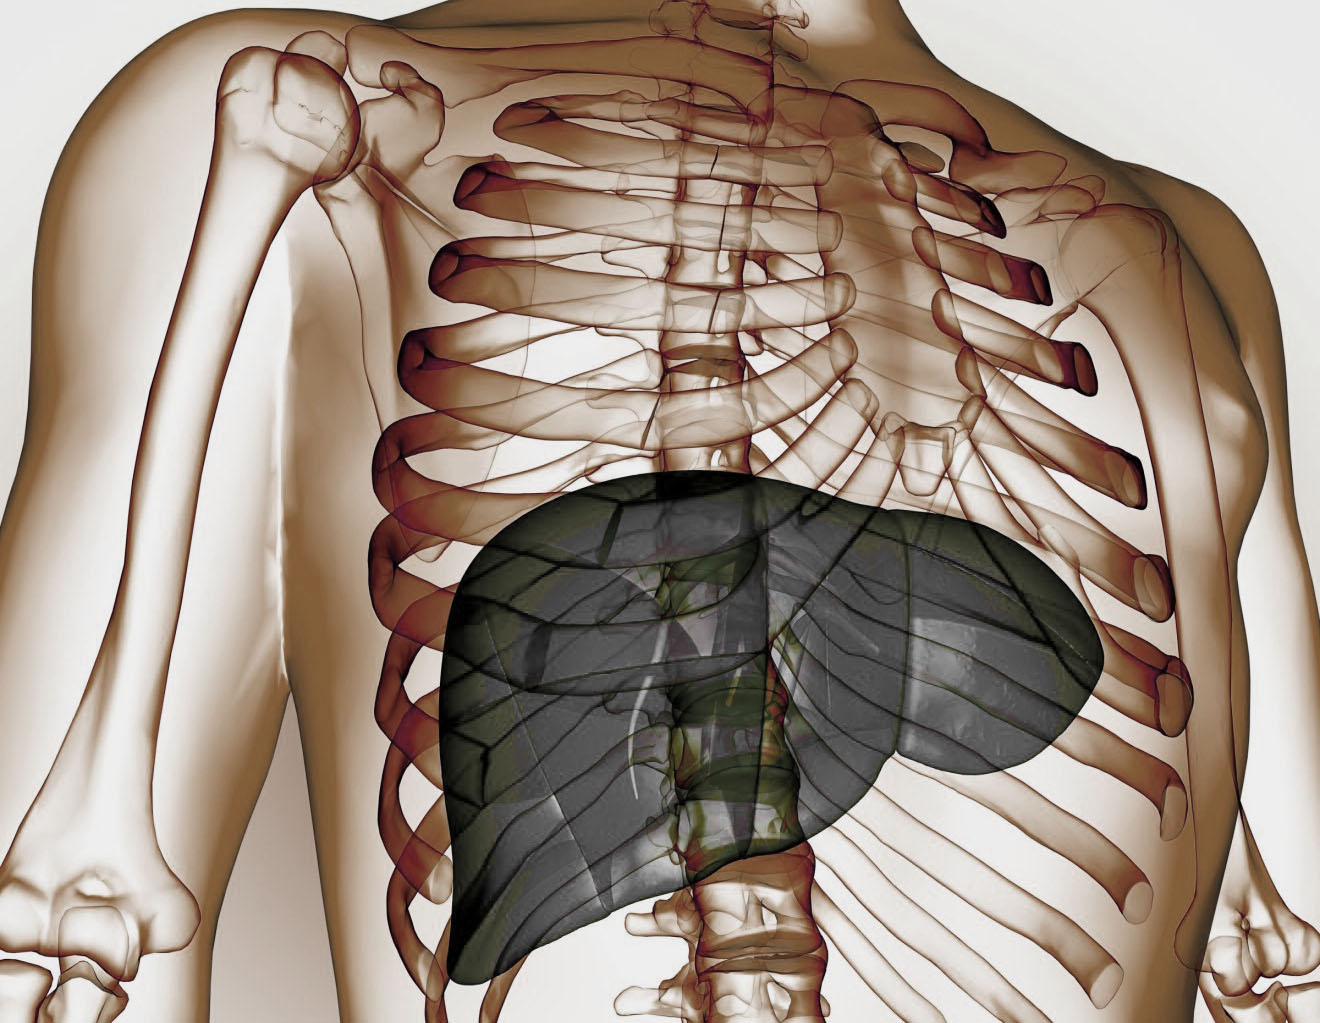

Το συκώτι είναι το κύριο όργανο αποτοξίνωσης του σώματος, παίζει επίσης κεντρικό ρόλο στην ομοιόσταση του μεταβολισμού και είναι ένας σημαντικός παράγοντας για τη σύνθεση, τον μεταβολισμό, την αποθήκευση και την ανακατανομή των υδατανθράκων, των πρωτεϊνών και των λιπιδίων.

Οι επεξεργασμένες τροφές που υπάρχουν γύρω μας σε αφθονία, οι τοξίνες και το περιβαλλοντικό στρες, η ταχεία αύξηση της παχυσαρκίας σε όλο τον κόσμο, σχετίζονται με την αύξηση του επιπολασμού της μη-αλκοολικής λιπώδους νόσου του ήπατος (NAFLD), γνωστή και ως λιπώδης διήθηση, καθιστώντας την, ως την πιο κοινή ασθένεια του ήπατος στις δυτικές κοινωνίες.

Η λιπώδης διήθηση (NAFLD) χαρακτηρίζεται από συσσώρευση λίπους εντός των ηπατοκυττάρων και μπορεί να εξελιχθεί σε μη-αλκοολική στεατοηπατίτιδα (NASH).

Το λιπώδες ήπαρ αποτελεί την πιο διαδεδομένη κατάσταση του ήπατος στις δυτικές κοινωνίες.

Παρουσιάζεται με ένα ευρύ φάσμα που κυμαίνεται από απλή στεάτωση ή μη – αλκοολικό λιπώδες ήπαρ (NAFL) για να αναπτυχθεί πλήρως στεατοηπατίτιδα με ή χωρίς ίνωση (ουλές). Αυτή μπορεί να εξελιχθεί σε ίνωση με αυξημένο κίνδυνο για την ανάπτυξη τελικού σταδίου ηπατικής νόσου ή ηπατοκυτταρικό καρκίνωμα (HCC).